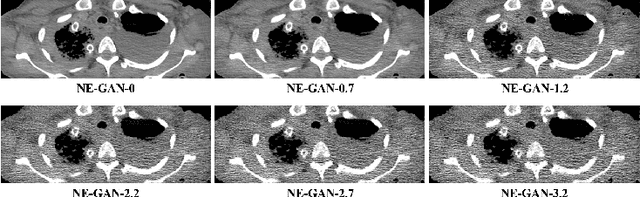

Abstract:We propose a Noise Entangled GAN (NE-GAN) for simulating low-dose computed tomography (CT) images from a higher dose CT image. First, we present two schemes to generate a clean CT image and a noise image from the high-dose CT image. Then, given these generated images, an NE-GAN is proposed to simulate different levels of low-dose CT images, where the level of generated noise can be continuously controlled by a noise factor. NE-GAN consists of a generator and a set of discriminators, and the number of discriminators is determined by the number of noise levels during training. Compared with the traditional methods based on the projection data that are usually unavailable in real applications, NE-GAN can directly learn from the real and/or simulated CT images and may create low-dose CT images quickly without the need of raw data or other proprietary CT scanner information. The experimental results show that the proposed method has the potential to simulate realistic low-dose CT images.